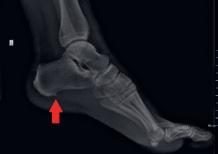

Petni trn (lat. plantarni fascitis) je koštana izraslina koja viri ispod petne kosti. Može se pojaviti kao reakcija na stres i upalu uzrokovanu plantarnom fasciopatijom. S vremenom tijelo reaguje na stres izgradnjom dodatog koštanog tkiva, odnosno petnog trna koji izaziva oštru i probadajuću bol, veoma sličnu boli koja se javlja kod plantarne fasciopatije. Najčešće je uzrok stres na ligamentima stopala. Javlja se obično između četrdesete i šezdesete godine života, podjednako kod žena i muškaraca. Većina ljudi i ne zna da ima trn u peti sve dok ne osjeti bolove u peti. Tada i zatraže pomoć.

Uzrok je dugotrajno naprezanje plantarne fascije i mišića stopala, posebno kod sportista i to najčešće atletičara.

Plantarna fascija je gusto, čvrsto vezivno tkivo koje se proteže od pete prema nožnim prstima. Pričvršćuje se na petnu kost i na bazu prstiju. Pomaže u hodu, prilikom podizanja pete kao i odraza preko prstiju.

Simptomi

• bol na petnoj kosti koji se može širiti i unutrašnjom stranom stopala

• prilikom jutarnjeg ustajanja iz kreveta karakteristična je pojava vrlo snažnog bola (kao da je ekser u peti) koji nestaje poslije desetak koraka. Ovakva bol se može pojaviti i prilikom započinjanja trčanja, kao i prilikom ustajanja nakon dužeg sjedenja.

Liječeje trna u peti

U prvom redu liječenje je usmjereno na identifikaciju i ispravljanje predisponirajućih faktora nastanka plantarnog fascitisa.

Liječenje trna u peti uključuje:

• odmaranje stopala i pete: ukoliko se trči ili džogira napraviti pauzu najmanje od petnaest do dvadeset dana kako bi se ublažili bolovi u peti

• primjena hladnih obloga na donji

dio stopala može pomoći u ublažavanju bolova u peti

• upotreba analgetika u kombinaciji sa kortikosteroidima te ponekad primjenom lokalnih anestetika u ampulama

• nošenje odgovarajuće obuće i po potrebi uložaka koji će pružiti oslonoc stopalu i ublažiti bol U više od devedeset odsto slučajeva nehirurško liječenje daje dobre rezultate.Ukoliko se poslije devet do 12 mjeseci konzervativnog liječenja ne uspiju ublažiti simptomi petnog trna, može se pristupiti hirurškoj intervenciji.